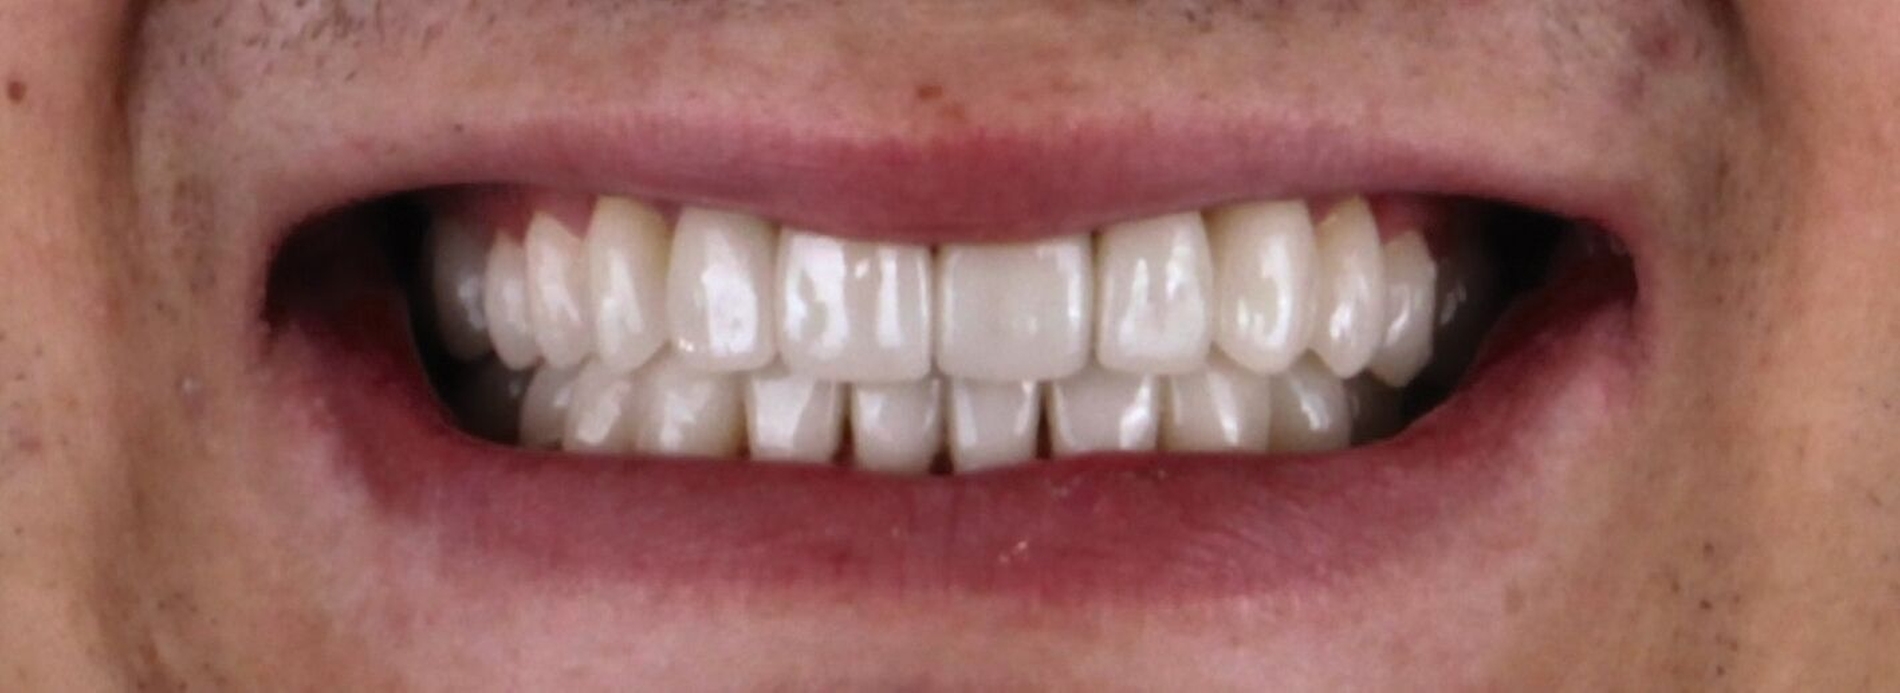

Der Patient konnte vollständig saniert werden und kam mit der neu eingestellten Bisshöhe sehr gut zurecht. Während der Behandlung wurden Ernährungshinweise gegeben, um die langfristige Haltbarkeit der Restauration zu gewährleisten. Eine besondere Herausforderung stellten in diesem Fall der angestrebte Ausgleich der verlorenen vertikalen Höhe und die Bestimmung der Myozentrikposition dar.

Fall II: Profifußballspieler

(Dr. Johanna Herzog, Dr. Florian Göttfert, ZAP edel&weiss, Nürnberg)

Ein Profi-Fußballspieler stellte sich in der Praxis zur sportzahnmedizinischen Überprüfung vor. Er klagte über Schmerzen an der linken Patellasehne. Sowohl in Ruhe als auch während Belastung beim Training oder im Spiel hatte der Sportler Probleme und immer wiederkehrende Schmerzen.